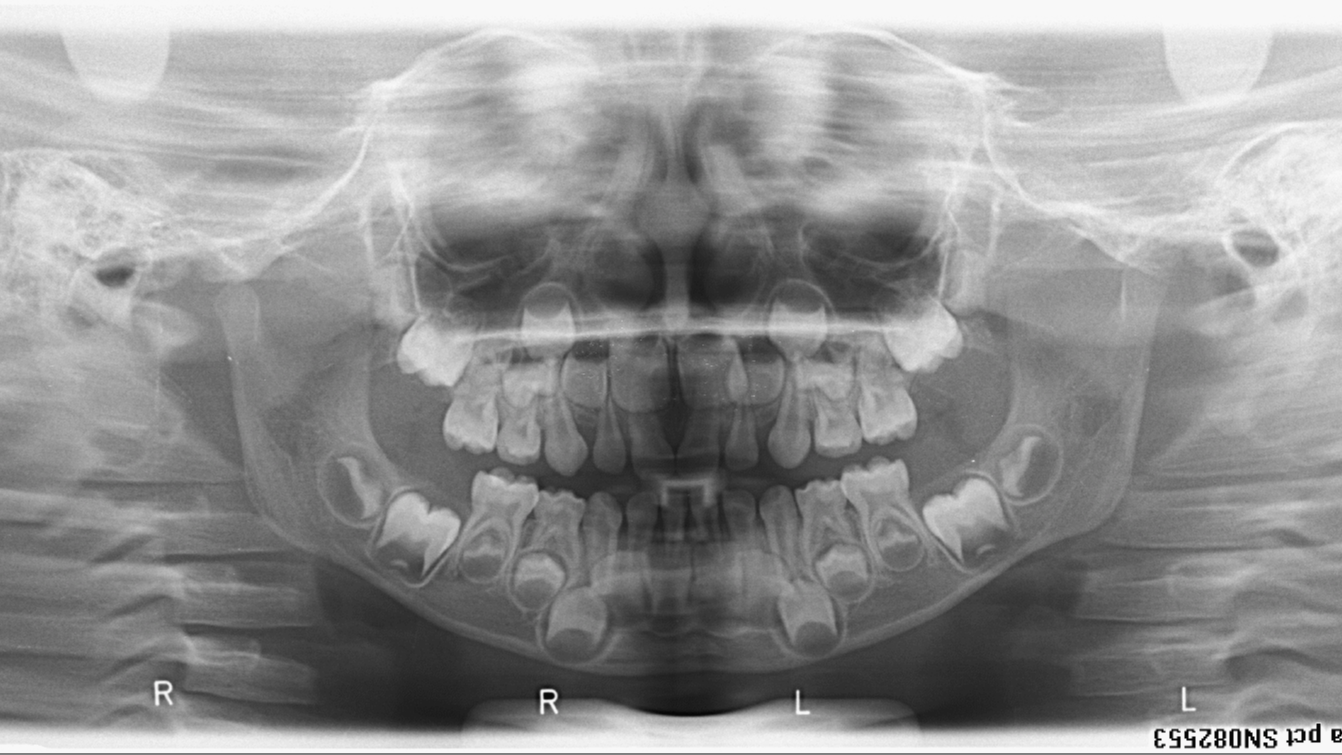

bilan des radiographies début et fin de traitement

bilan début fin de traitement